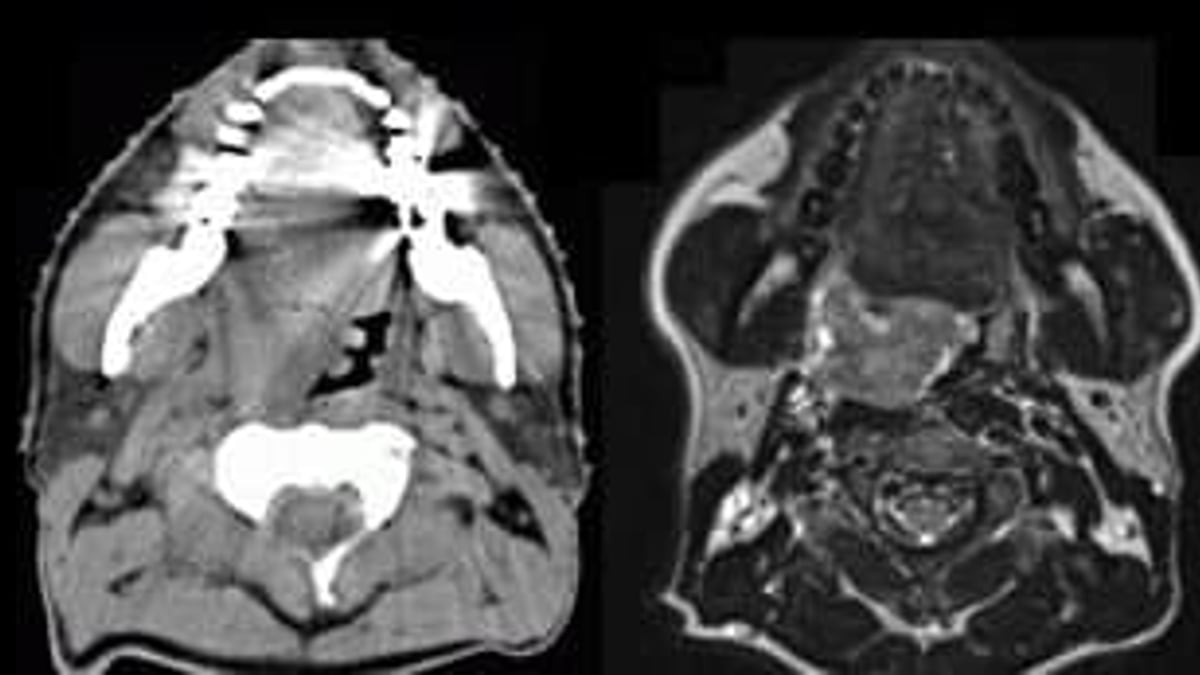

Till vänster röntgenbild med datortomografi (DT) i höjd med munhålan, till höger motsvarande bild av samma patient med magnetresonanstomografi, MRI, med tydligt förbättrad mjukdelskontrast.